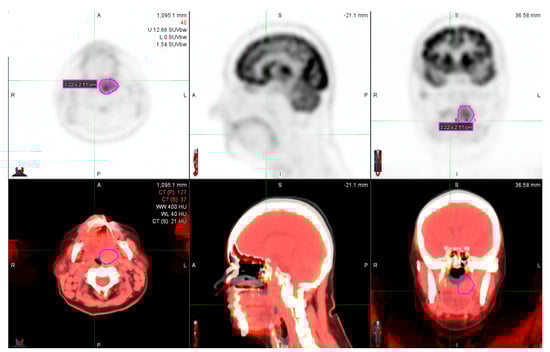

We used the Statistica 13.0 (Statsoft, Poland; available upon the individual license) application to perform the necessary analyses. We used the MiM 7.0 (MiM Software Inc. Cleveland, Ohio, USA); no commercial license available, (Figure 1 and Figure 2) software for contouring and SUVmax surrogates’ calculation. We have used the Philips Gemini TF 16 (Ohio, Cleveland, USA) PET/CT scanner in all patients.

Figure 2. Left palatine tonsil primary tumor (MiM 7.0 fusion) obtained in one patient – initial scanning at 60min.p.i. (upper images: PET, below—PET/CT fusion).